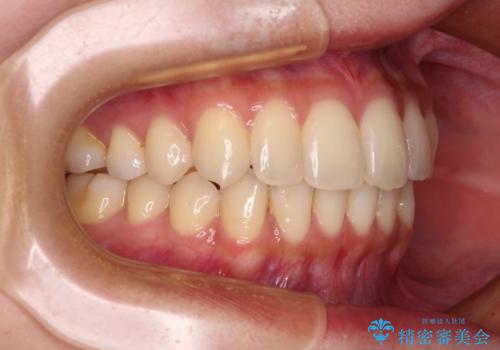

- 前歯のデコボコと強い咬みしめを気にして来院された患者様です。

インビザラインを用いて、前歯の叢生を解消するとともに、ディープバイトを改善していくこととしました。

海外へ転居する予定があったため、1日22時間以上の装着時間をしっかりと守っていただき、予定期間よりも早く、思っていた以上にきれいに仕上げることができました。